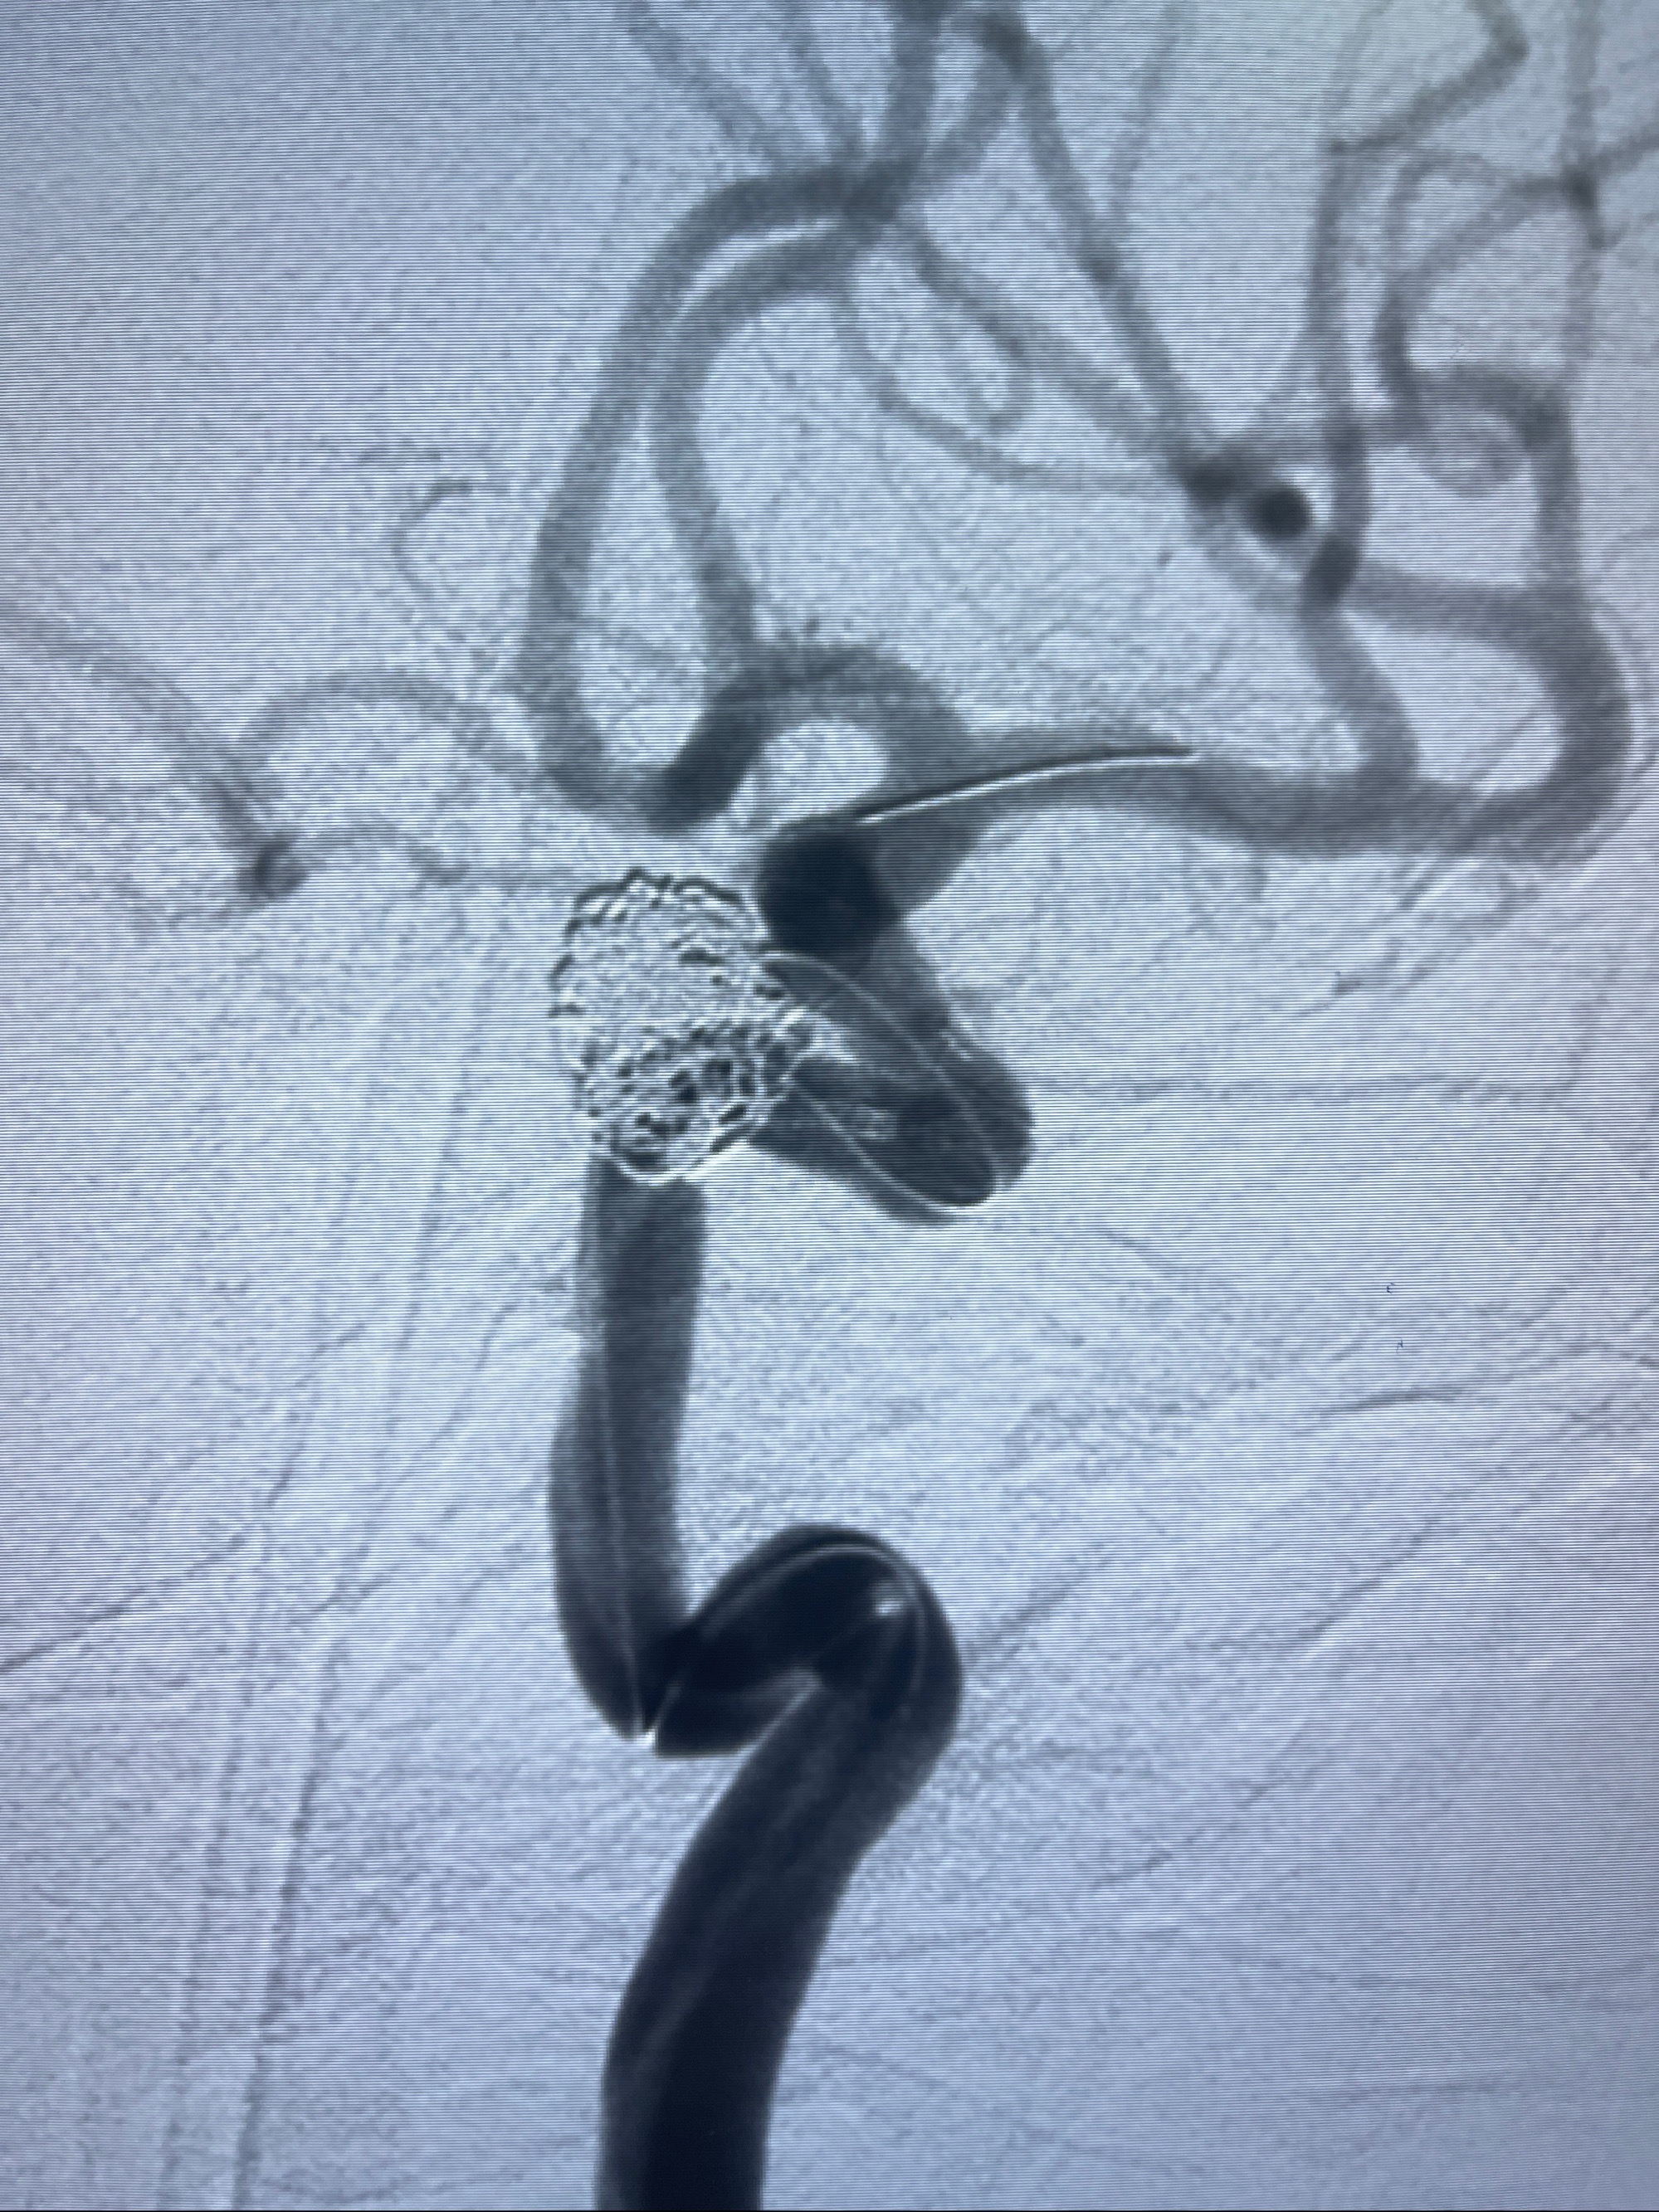

2023-08-30DSA:左侧颈内动脉眼动脉动脉瘤,约3*9.2*7.3mm大小

密网支架辅助栓塞

- Tubridge 4.0-20mm密网支架

- 加奇微弹簧圈:7*30/6*20/5*20/2*8

术后3D显示支架贴壁佳